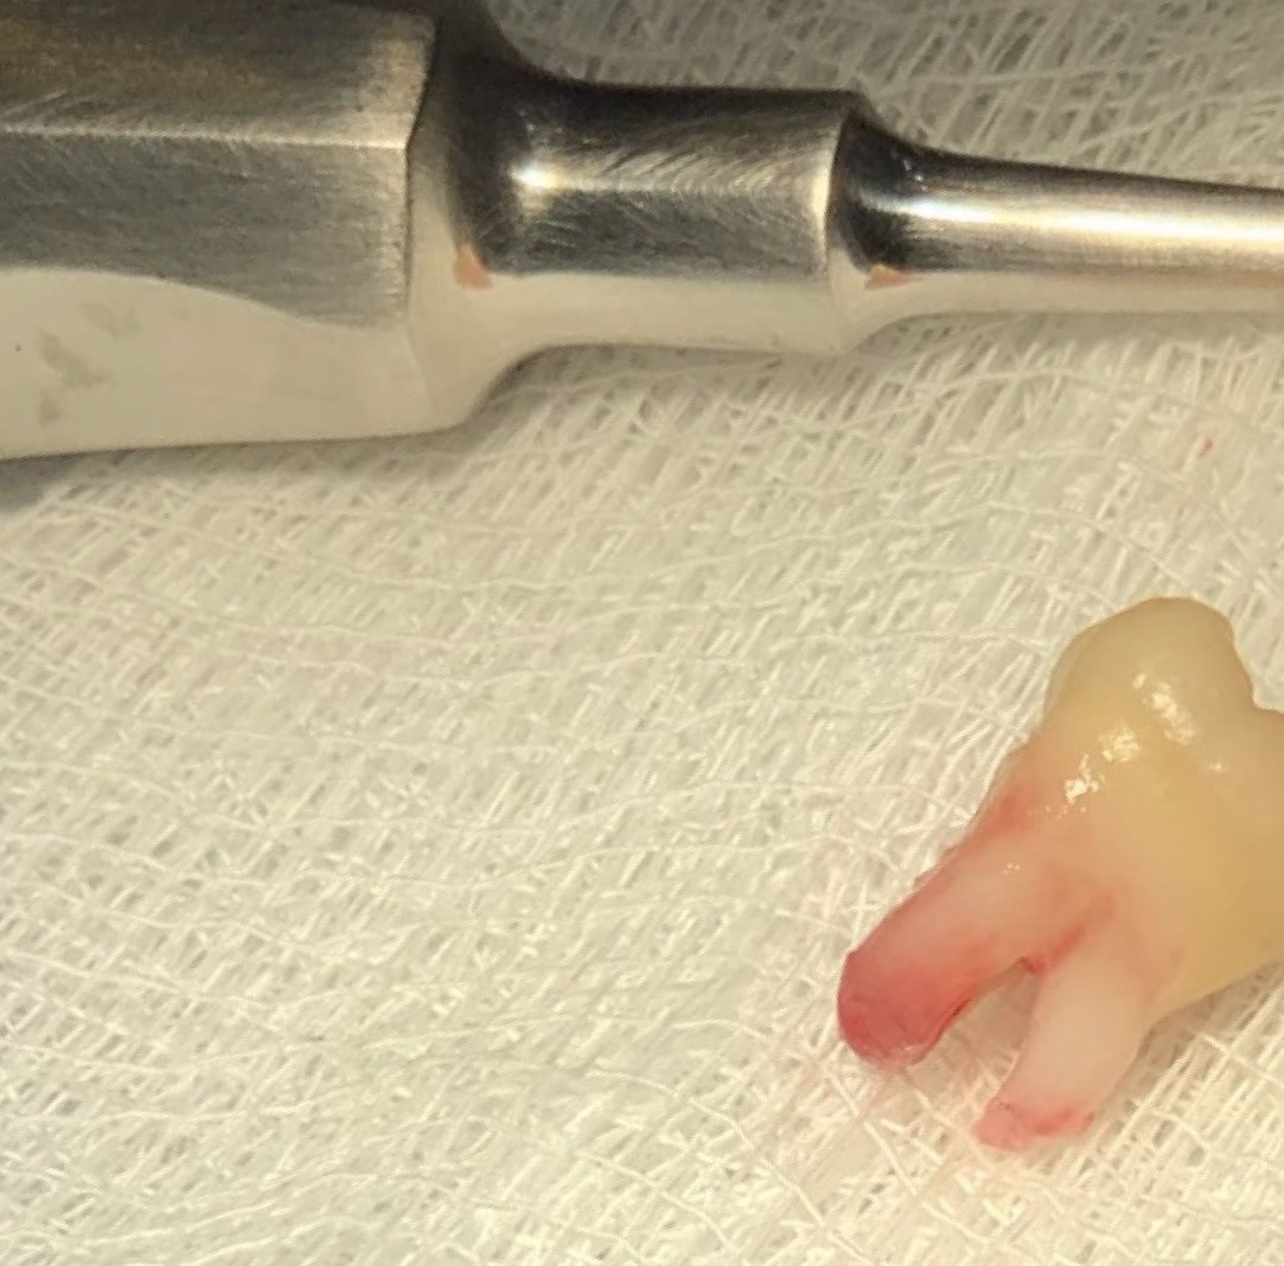

Se usa instrumentos especializados para la extracción del diente o muela.